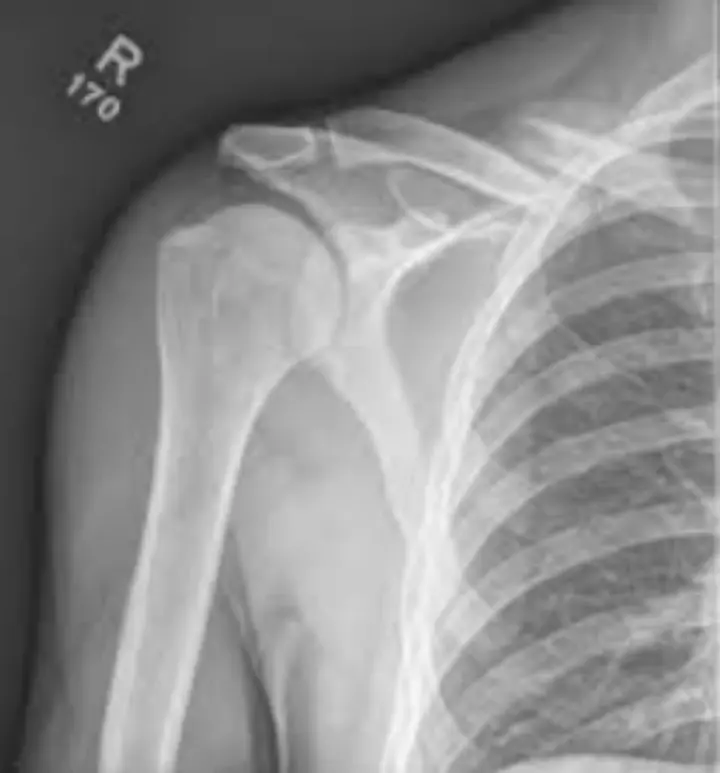

▎锁骨骨折X线

如上图所示,锁骨骨折后没有固定的情况下骨折断端相互滑动嵌插,本身就可能造成血管神经损伤,患者在行走移动的过程中容易受到碰撞,大大增加了这种风险。

视频中患者应该是上肢骨折或者锁骨骨折。这种情况下,行走过程中若出现下意识的动作或者人员意外碰撞,轻则导致骨折移位,治疗难度成倍增加,重则导致神经血管损伤。

锁骨紧邻锁骨下动脉和臂丛神经,骨折断端往往呈斜形,非常锋利,没有固定的情况下受到人员碰撞等情况导致骨折端滑动,进而损伤血管、神经,造成严重损伤的可能性很大。如为肱骨骨折,桡神经紧贴肱骨后方,肱骨下端骨折时易发生桡神经损伤,如果没有固定,损伤风险大大增加。需要特别提醒的是,神经损伤目前没有特效疗法,断裂后造成永久性伤害的可能性很高。